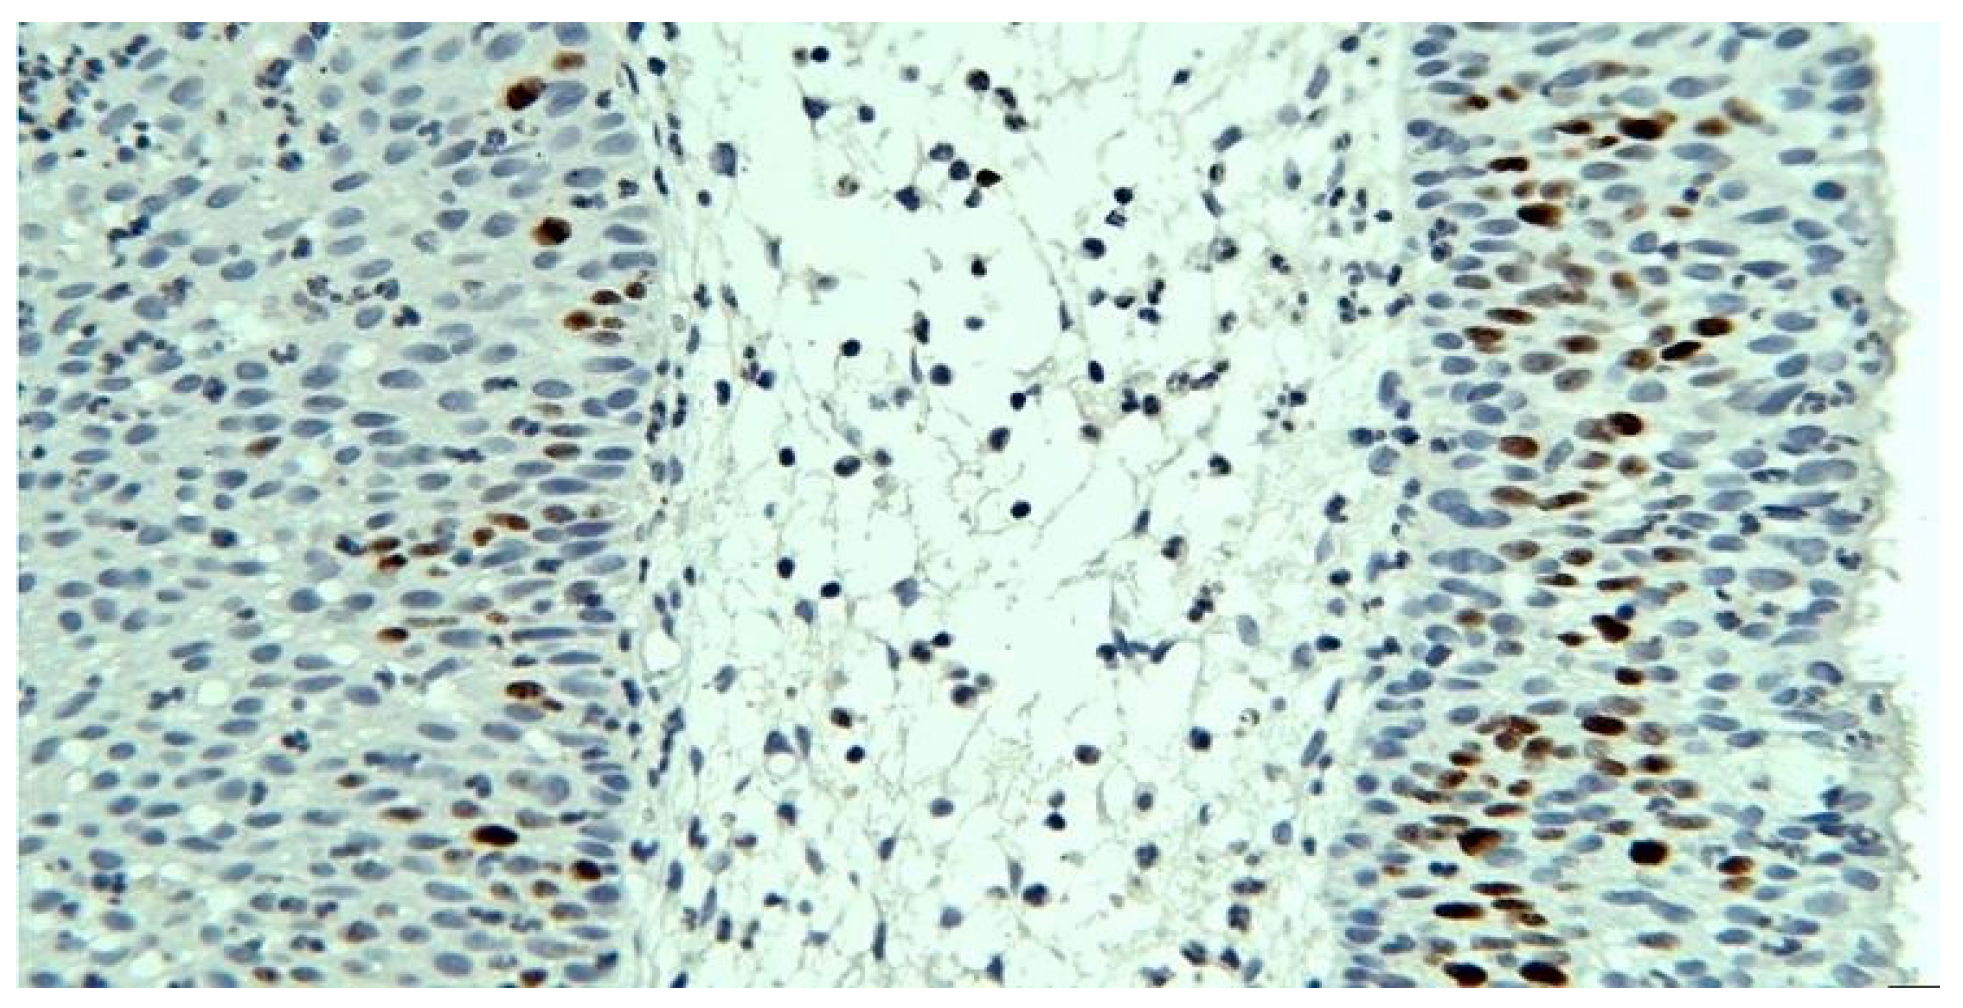

P53 immunolabeling – nuclear positive in the basal layer of the epithelia, in less of 10% of the cells, more frequently in the case of squamous epithelia (Figure 11).

Figure 11.

p53, squamous epithelium, x200.

In the present case, p53 immunolabeling reveals a low presence of it (in less than 10% of the cells), more frequently in the case of squamous epithelia (tissue with more pronounced turnover), a fact that correlates with an increased potential for malignancy.